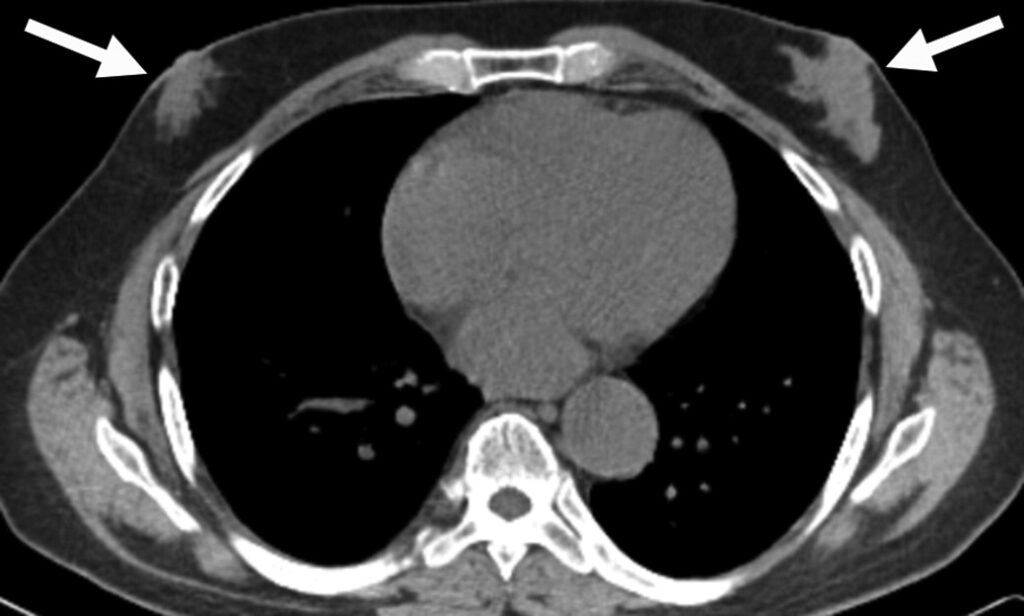

Uomo di 75 anni con tumore alla prostata.

L’immagine planare whole-body in proiezione anteriore della scintigrafia ossea mostra due foci di captazione nella parte inferiore del torace (frecce), sovrapposti alle coste anteriori, inizialmente ritenuti localizzati nelle coste stesse.

L’acquisizione tomografica ibrida risolve definitivamente l’ambiguità spaziale creata dall’immagine planare. Le fette assiali dimostrano che i due focolai di ipercaptazione risiedono nei tessuti molli superficiali sovrastanti le coste, localizzandosi esattamente nel tessuto mammario retroareolare bilaterale.

La captazione simmetrica a livello mammario in un paziente di sesso maschile trattato per neoplasia prostatica è indicativa di ginecomastia indotta da farmaci. L’ipertrofia benigna della ghiandola (che capta il radiotracciante in via extra-ossea) è un ben noto effetto collaterale della terapia di deprivazione androgenica (o della terapia estrogenica).